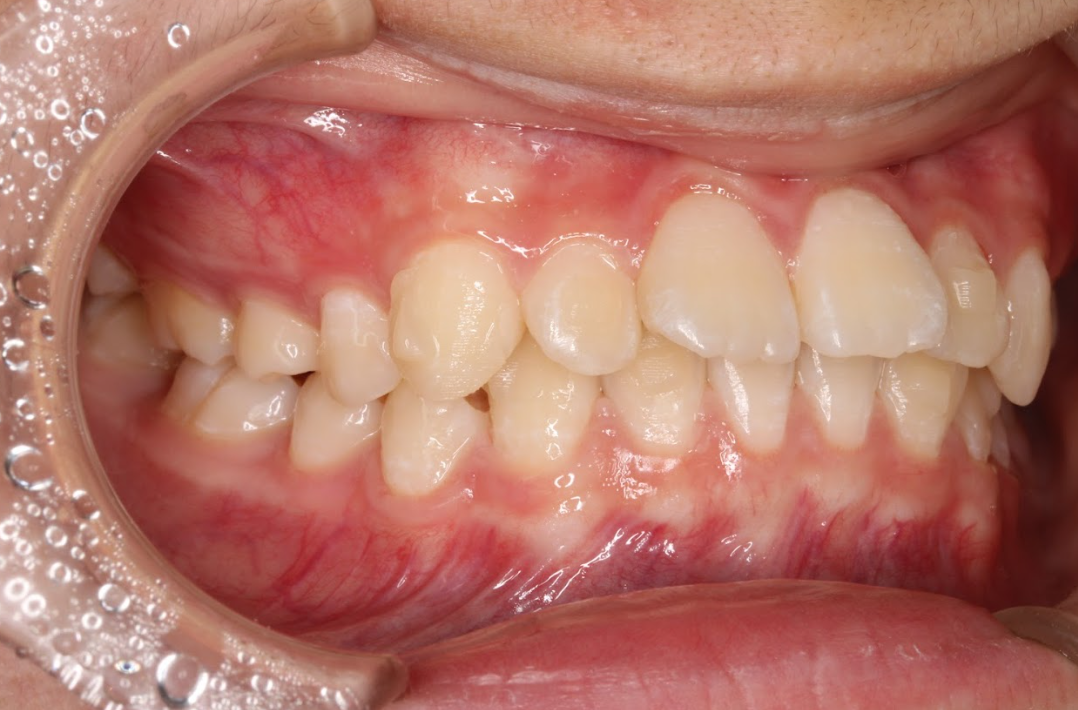

軽度の出っ歯

上の前歯が前方に突出している「軽度の出っ歯」は、上の歯だけを矯正して改善できることがあります。特に、下の歯との噛み合わせに問題がなく、前歯の傾斜によって出っ歯になっているケースでは、インビザラインによって前歯を内側に引き下げることで見た目を整えることができます。

ただし、出っ歯の原因が骨格的な問題(上顎骨の過成長や下顎骨の劣成長)である場合や、下の前歯との干渉が強い場合には、上下の矯正や他の治療法が必要になることもあります。